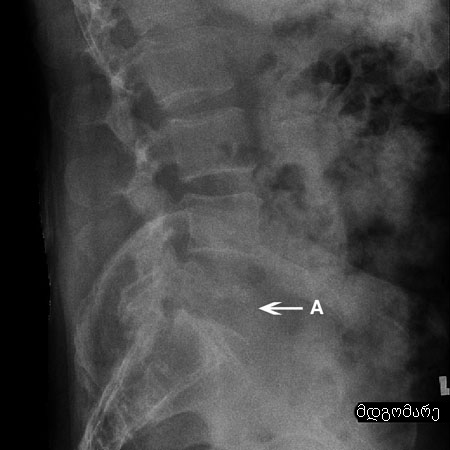

სიმსივნის რენტგენი: ლიმფომა (A), ხერხემლის L5 მალის დესტრუქციით

ექიმ Dr K. Singh საკუთრება; გამოყენებულია ნებართვით